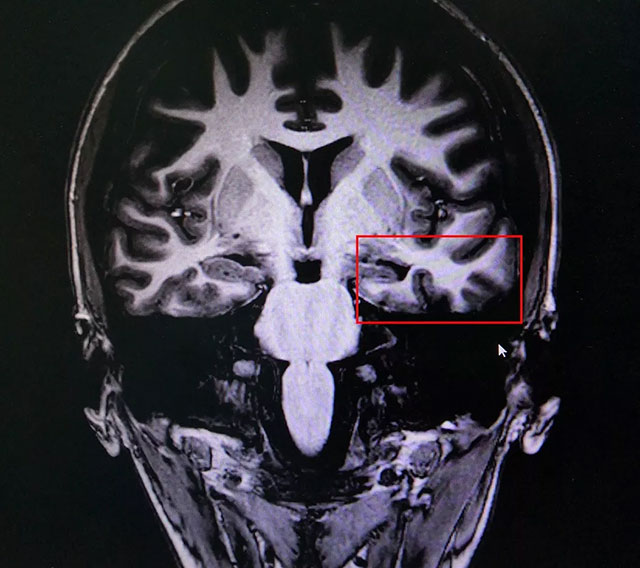

來(lái)院后,腦電監(jiān)測(cè)崔麗華主任應(yīng)用先進(jìn)的美國(guó)尼高力長(zhǎng)視頻腦電圖儀為雯雯做了24小時(shí)腦電監(jiān)測(cè)。在監(jiān)測(cè)中,從事臨床及腦電圖工作30余年的崔主任敏銳地發(fā)現(xiàn)了異常腦電波,左側(cè)蝶骨電極,顳區(qū)局限性異常放電,建議進(jìn)一步檢查。隨后雯雯接受了頭顱海馬MRS、PET-CT、心電圖、肝腎功能、電解質(zhì)、血尿糞常規(guī)等全面詳細(xì)的檢查。

▲ 患者癲癇病灶區(qū)域

藍(lán)十字腦科功能神經(jīng)外科主任楊忠旭博士認(rèn)真查看了雯雯各項(xiàng)檢查報(bào)告并聽(tīng)取相關(guān)病情匯報(bào)后指出,一般幼時(shí)突發(fā)高熱驚厥,尤其伴有抽筋的癥狀,會(huì)導(dǎo)致大腦缺血、缺氧,而海馬對(duì)這種情況的耐受較差,極易造成其內(nèi)的神經(jīng)細(xì)胞受損,時(shí)間長(zhǎng)了就會(huì)發(fā)展成海馬硬化,成年后,有近一半以上的病人會(huì)因此患上頑固性癲癇。

雯雯癲癇診斷明確,系統(tǒng)內(nèi)科藥物治療不佳,確診為:難治性癲癇。應(yīng)用現(xiàn)代神經(jīng)影像學(xué)技術(shù)和電生理監(jiān)測(cè)技術(shù),能明確引起癲癇發(fā)作的的“責(zé)任病變”,手術(shù)指征明顯,未見(jiàn)明顯手術(shù)禁忌癥。楊教授為她制定了周全的手術(shù)方案并做好充分準(zhǔn)備。